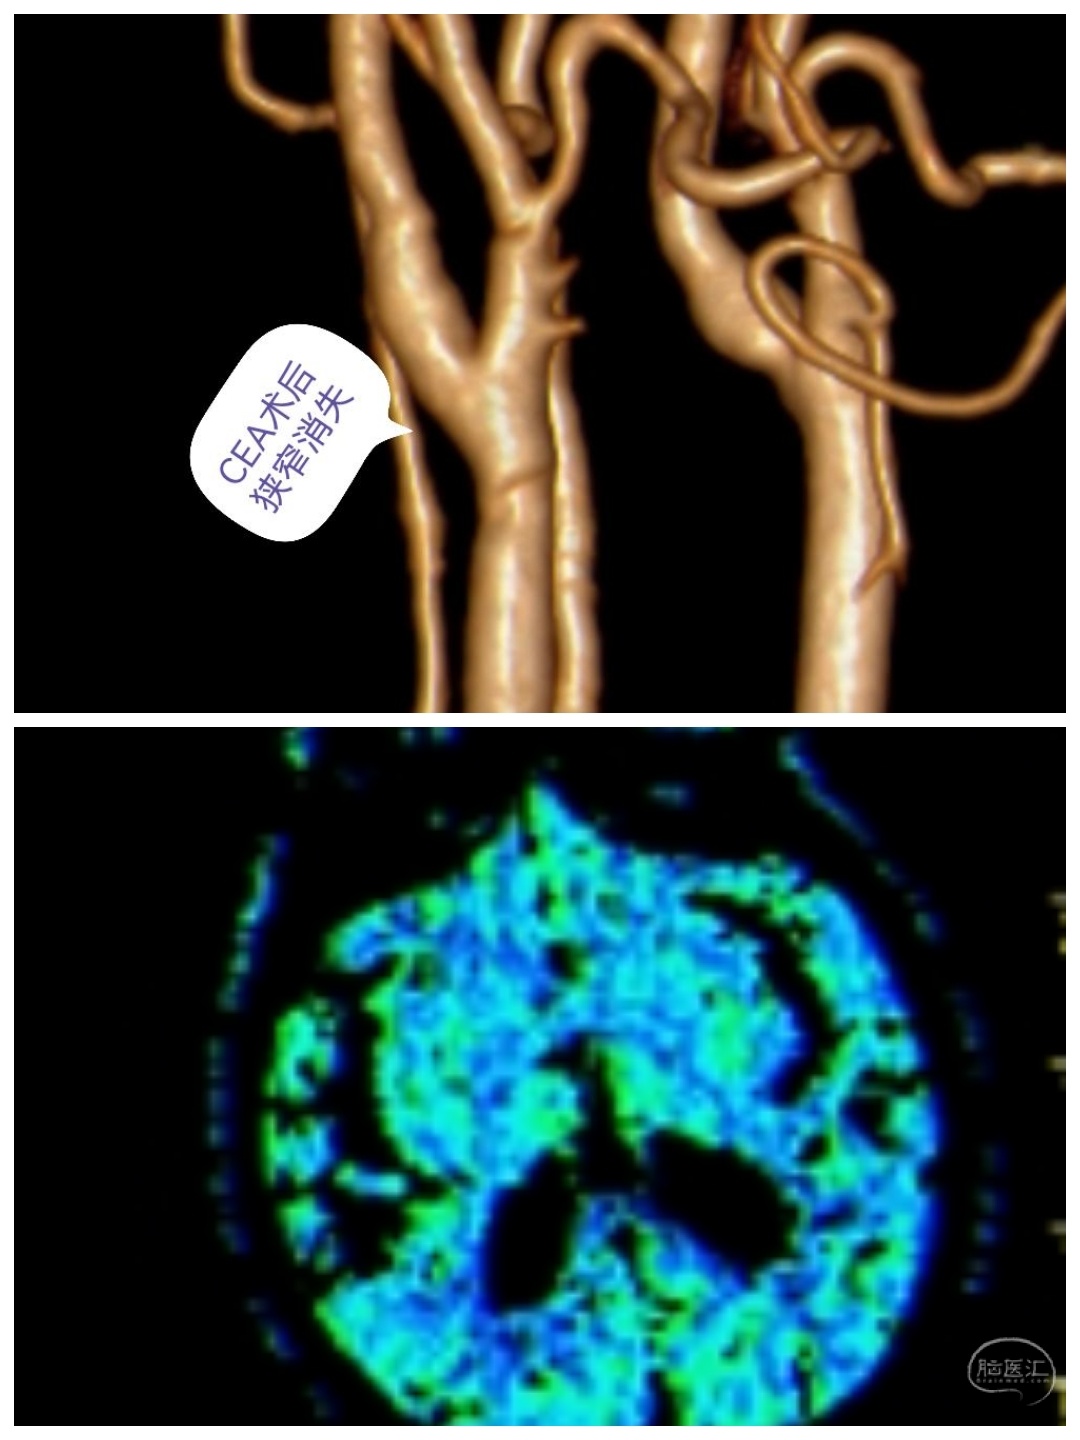

MR提示右侧多发腔隙性脑梗塞,CTA提示右侧颈内动脉起始处狭窄90%。

术后随访

CTA提示右侧颈内动脉狭窄消失,患者头晕症状消失